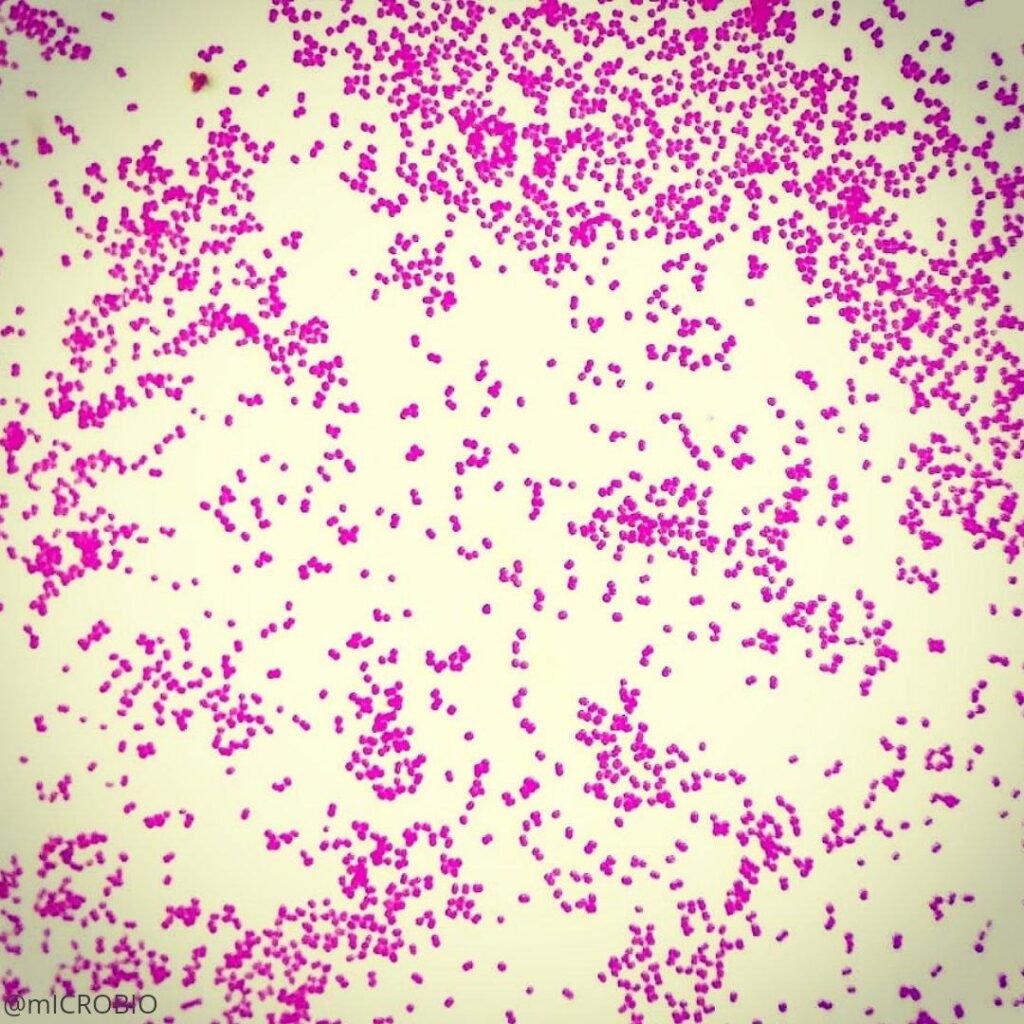

Acinetobacter baumannii is a Gram-negative, aerobic pleomorphic coccobacillus.

- Gram reaction: Gram-negative

- Arrangement: Occurs singly, in pairs or short chains

Acinetobacter baumannii are non-motile as they lack flagella, but exhibit motility by swarming or twitching with the help of Type IV pili. They are non-fermenting, non-fastidious bacteria. Under microscopy, the bacterial cell appears as a small, pink coccobacilli.